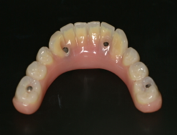

2.歯の形はほぼ天然歯があった時と同じになるので取り外しの義歯に比べて違和感がなく、手入れもインプラントの本数を少なくすることにより、清掃もし易くなっています。